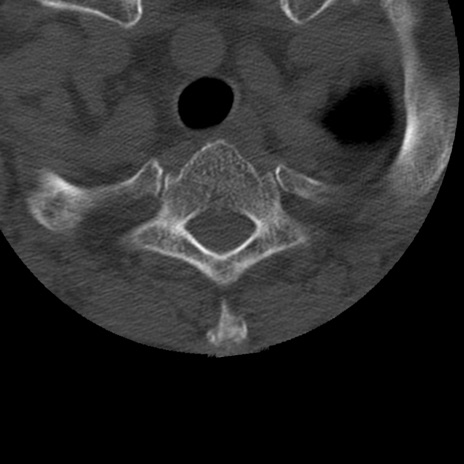

症例50 頚椎CT(横断像)

矢状断像